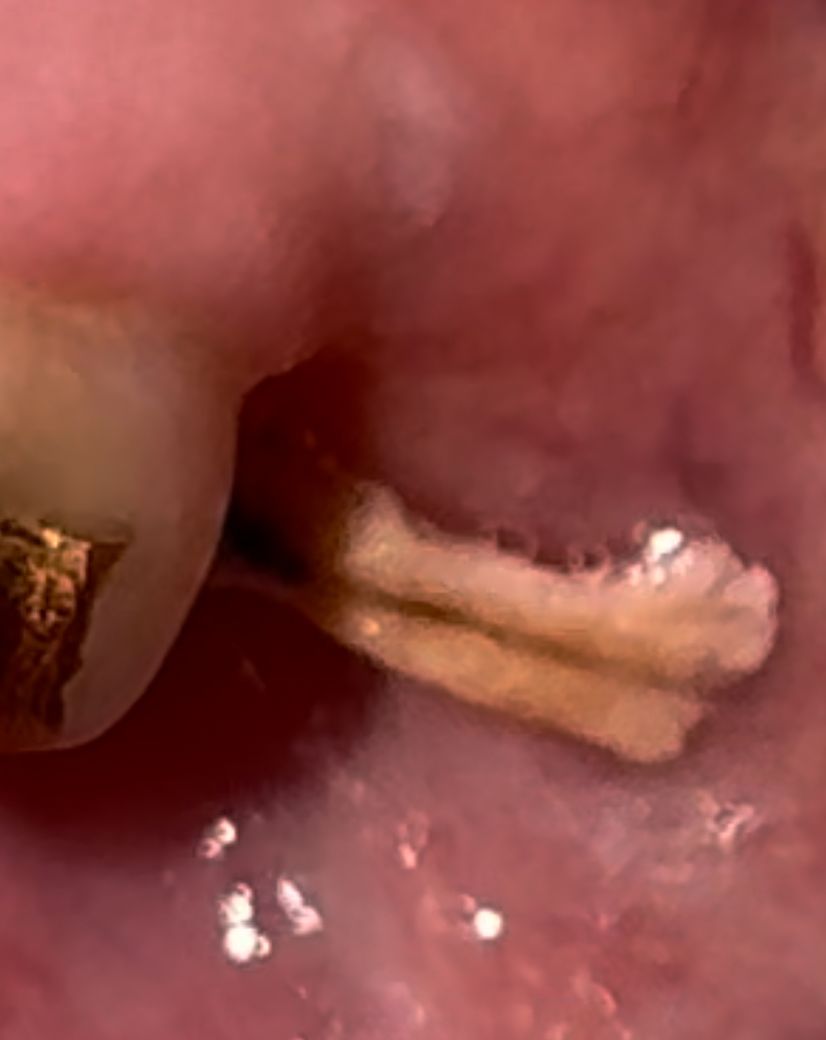

사랑니 발치한 자리에 이게 뭔가요??

사랑니 발치 후 3-4주 정도 되었고, 실밥 푼지는 2주 정도 된 상태입니다.

이렇게 생긴 것이 혀로 만졌을 때 움직이는 상태인데, 이게 무엇인가요??

사진으로는 정확한 확인을 하긴 힘들어 보입니다. 하지만 발치를 했을 때 내부에 뼈가 잘 차오르도록 콜라겐 충전재를 넣는 경우가 있습니다. 이런 경우에는 하얀색 물질이 나올 수 있습니다. 정확한 확인을 위해서 치과에서 진료받고 확인해 보는 것이 좋습니다

음식물등이 제대로 제거되지 않아서 그럴수도 잇을것같습니다.치과에 가셔서 소독을 다시 받아보시는게 좋을것같습니다.